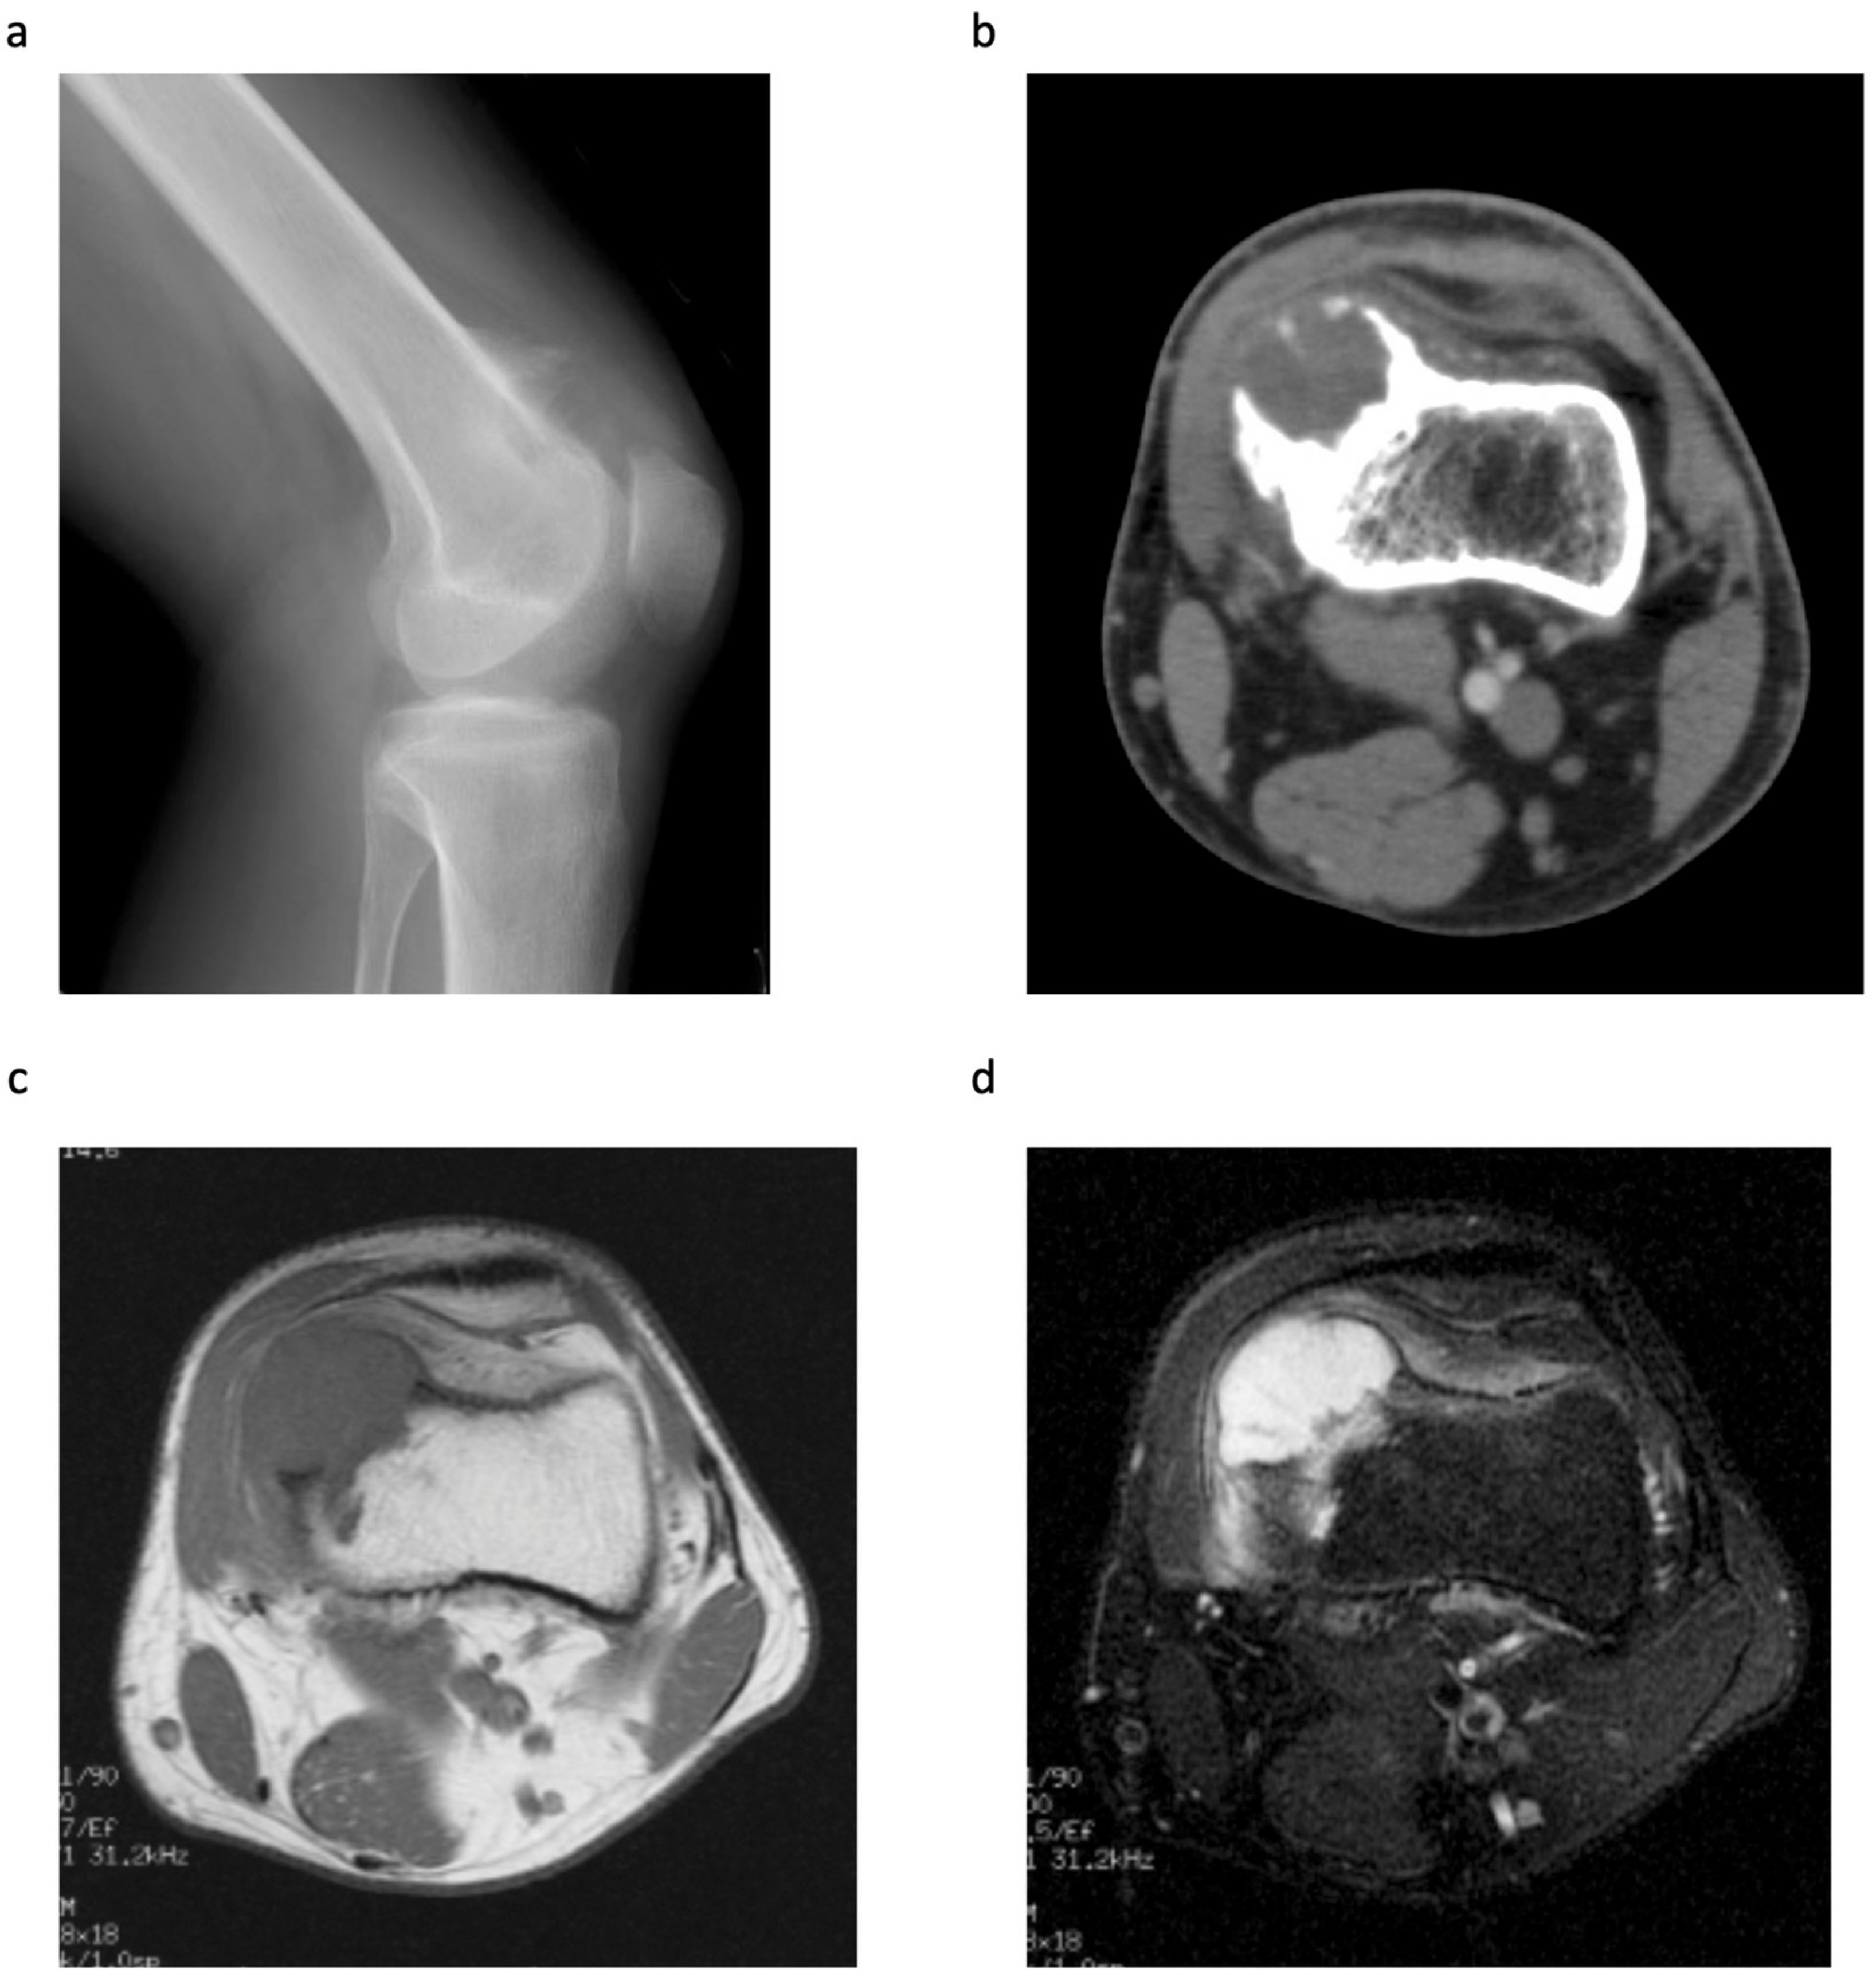

Clinical, Radiological, and Histopathological Characteristics of Periosteal Chondrosarcoma with a Focus on the Frequency of Medullary Invasion

| Case | Sex | Age | Symptoms | Duration of Symptom (Months) | Site | Size (cm) | Cortex | Surgical Margin | Reconstruction | Histological Grade | Follow-Up Period (Months) | Recurrence | Metastasis |

|---|---|---|---|---|---|---|---|---|---|---|---|---|---|

| 1 | M | 22 | pain swelling | 1 1 | distal femur metaphysis | 2 × 1 × 2.5 | erosion | wide | β-TCP | I | 1 | − | − |

| 2 | M | 36 | swelling | 2 | distal femur metaphysis | 2 × 1.5 × 2 | no change | wide | bone autograft + plate | II | 72 | − | − |

| 3 | M | 23 | pain swelling | 6 3 | distal femur metaphysis | 6.0 × 4.0 × 3.0 | thickening | wide | DFR | II | 134 | − | − |

| 4 | M | 37 | swelling | 12 | fibula diaphysis | 5.5 × 2.5 × 3.5 | erosion | marginal | − | I | 59 | − | − |

| 5 | M | 41 | pain | 2 | proximal humerus metaphysis | 5.2 × 4.8 × 4.4 | no change | wide | PHR | II | 77 | − | − |

| 6 | M | 49 | swelling | 2 | pubis | 8.8 × 5.4 × 5.4 | thickening | wide | − | I | 36 | − | − |

| 7 | M | 35 | swelling | 1 | proximal humerus metaphysis | 7.5 × 5.5 × 5.5 | thickening | wide | bone autograft + plate | II | 32 | − | − |

| Case | Medullary Invasion (MRI) | Medullary Invasion (Pathological) | Distance from the Cortex to the Deepest Lesion of the Intramedullary Tumour (mm) | Skip or Continuous from Periosteal Tumour |

|---|---|---|---|---|

| 1 | − | + | 15 | continuous |

| 2 | + | + | 15 | continuous |

| 3 | + | + | 25 | skip |

| 4 | − | + | 3 | skip |

| 5 | + | + | 18 | skip |

| 6 | − | + | 1 | continuous |

| 7 | − | − |